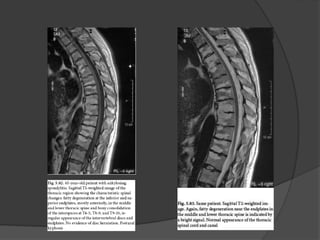

RM

Exames de Imagem Radiografias simples;  TC;  RNM.